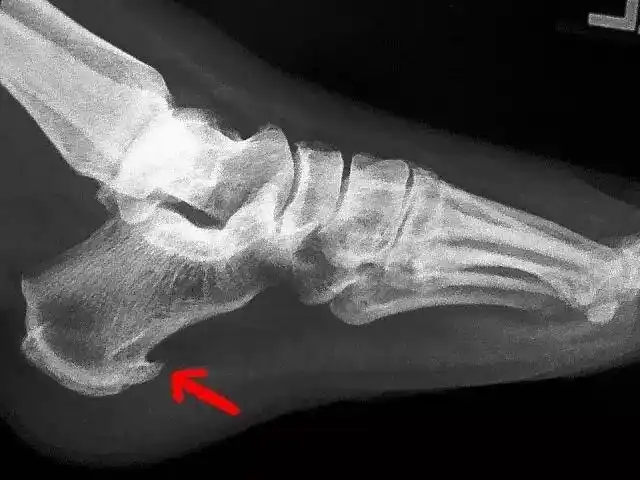

脚后跟长了骨刺怎么办